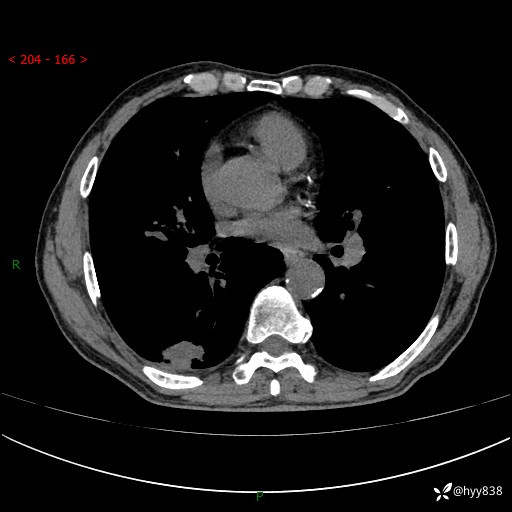

老年男性,发现右下肺结节3天。结节+卫星灶,似曾相识---结果公布~

简要病史:患者3天前于我院常规体检时行胸部CT提示“右下肺结节35mm*24mm”,自觉无发热、咳嗽、咳痰,无胸痛、咯血、气促加重,无声嘶、吞咽困难,无乏力、盗汗、体重减轻等不适。为求进一步诊治,入我院求诊,门诊以“右下肺结节待查”收入我科。患者3天前于我院常规体检时行胸部CT提示“右下肺结节35mm*24mm”,自觉无发热、咳嗽、咳痰,无胸痛、咯血、气促加重,无声嘶、吞咽困难,无乏力、盗汗、体重减轻等不适。为求进一步诊治,入我院求诊,门诊以“右下肺结节待查”收入我科。 起病以来,患者精神、食欲、睡眠可,体力稍差,大小便正常,体重无明显变化。

辅助检查:CT

临床诊断:肺结节

胸部CT平扫